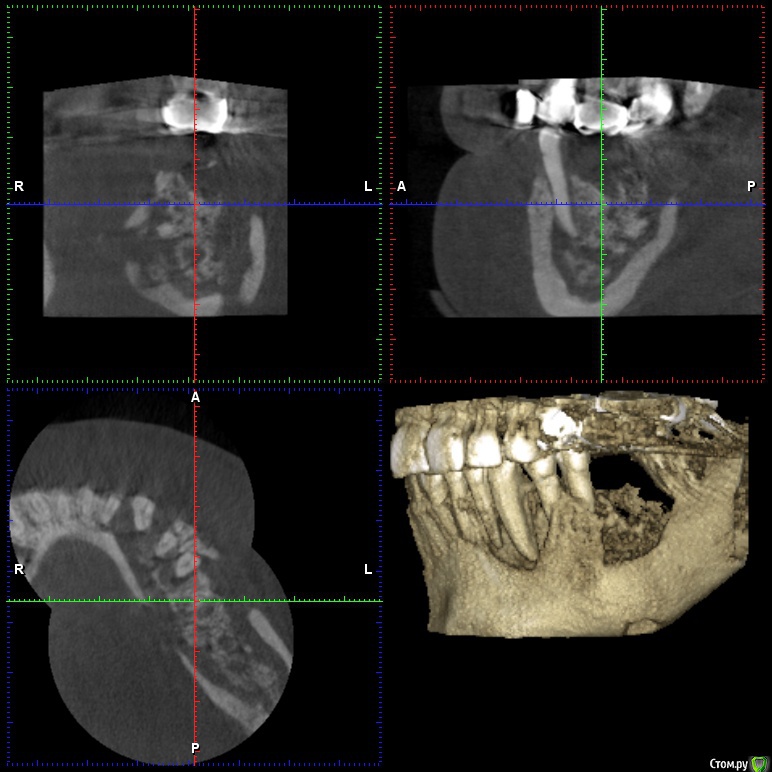

gum Опубликовано 5 апреля, 2017 Поделиться Опубликовано 5 апреля, 2017 Здравствуйте, обратилась пациентка, лет 7 назад тоже была на бисфосфонатах (онкология) года 4-5 назад удалены по одному зубу справа и слева, начался остеонекроз, с типичной картиной для таких случаев, потом она пропала и вот сегодня пришла, сделали кт, все видите сами, плюс наличие свищей, секвестры в полости рта. Вопрос: где в России или за ее пределами занимаются такими пациентами, куда ее направить для резекции и послед реконструкции? Ссылка на комментарий

kriokov Опубликовано 10 октября, 2024 Автор Поделиться Опубликовано 10 октября, 2024 (изменено) Случай из практики , поделился коллега. Пациентке в 2019 году установлены имплантаты и НКР. В 2022 обнаружена злокачественная опухоль молочной железы. В дальнейшем метастазы в позвоночник, терапия , в том числе и бифосфонатами. Коллега делал осмотр и реннтгенографию в 2022, с его слов на снимках была убыль кости в области имплантата 37 на два витка. На сегодня жалобы пациентки- боли , особенно в вечернее время. Пациентка лечиться у онкологов с применением бифосфонатов. Изменено 10 октября, 2024 пользователем kriokov неправильно вставил ОПТГ Ссылка на комментарий